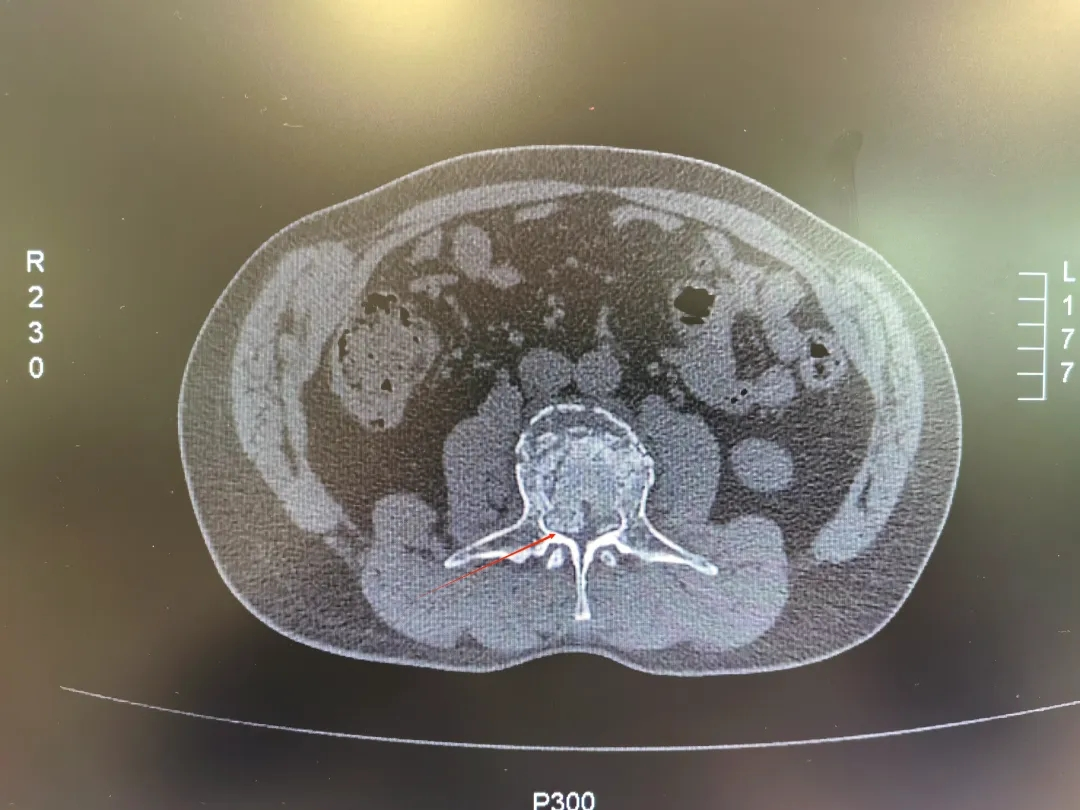

骨折块压迫脊髓,患者命悬一线

该患者为一名52岁中年男性,在工作时不慎从高处坠入3米深坑中,重伤腰部,被紧急送至西安市中心医院经开院区急诊科。急诊科请骨科张强医师紧急会诊,张强医师对患者进行详细查体后,第一时间要求完善患者相关腰椎X线、腰椎CT三维重建及腰椎MRI等检查,及时向刘邦定主任进行汇报,入院时,患者双下肢已完全不能活动,感觉减弱,情况万分危急。经过紧急CT及核磁共振检查,被确诊为“腰3椎体爆裂性骨折伴不全瘫痪”,碎裂的骨块如同“炸弹的弹片”一样,严重侵入椎管,压迫了支配下肢感觉和运动的脊髓神经。这正是导致患者瘫痪的直接原因。

骨科团队联合麻醉科、手术室、影像科等多学科专家,迅速为患者制定了详尽的手术方案:后路腰3椎体爆裂骨折切开复位、椎管减压术。手术的核心目标非常明确:第一,彻底解除对脊髓的压迫,为神经功能恢复创造空间;第二,重建脊柱的稳定性,为患者日后站立和行走打下基础。